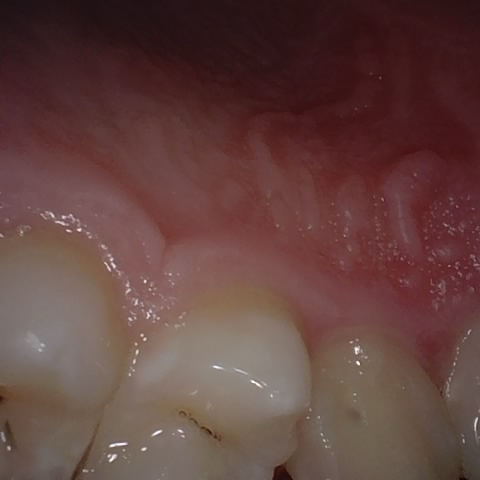

Annotated as "Good"